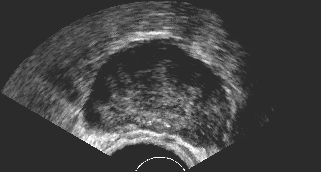

It is a challenge to validate any approach to segmentation. One has to measure the accuracy of the segment against ground-truth images. Ideally, if we have many users available to segment images, we can build “consensus segments”, or gold standard, to make more reliable measurements. Of course, this is usually not feasible with real images, for which there is no gold standard. Hence, we generated synthetic images whose gold segments were known a priori. For this reason, we used synthetic images that simulate transrectal ultrasound (TRUS).

TRUS images of prostates may be used to both diagnose and treat prostate diseases such as cancer. Starting with a set of prostate shapes , we created random segments through combinations of those priors, adding noise along with random translations and rotations, and we distorted the results with speckle noise and shadow patterns. Each image is thus created from its gold . Consequently, we can simulate user delineations by manipulating via scaling, rotation, and morphological changes, and we can simulate edits by running active contours with variable user-simulating parameters. The variability of user delineations was simulated according to several factors: error probability (), anatomical difficulty ( out of ), and the scaling factor for morphology (form to ). The user was modelled according to the level of experience (a random number from ), the user’s attention (a random number from ), and the user’s tendencies in terms of the segment size (a random number from ), whether tending to draw contours that are relatively small () or large ().

We generated 500 images from their corresponding gold-standard images111All images and their segments are available online: http://tizhoosh.uwaterloo.ca/. Furthermore, we generated 20 different segments for each image, assuming that there were 20 users. Figure 4 shows five examples of real and synthetic TRUS images. One should bear in mind that the purpose here was not to simulate the images realistically, but rather to have a base from which to generate variable segments from a perfect segment. Figure 5 shows an example of the gold segments and simulated user contours. The variability, coupled with the gold segment, is what is needed in our experiments.